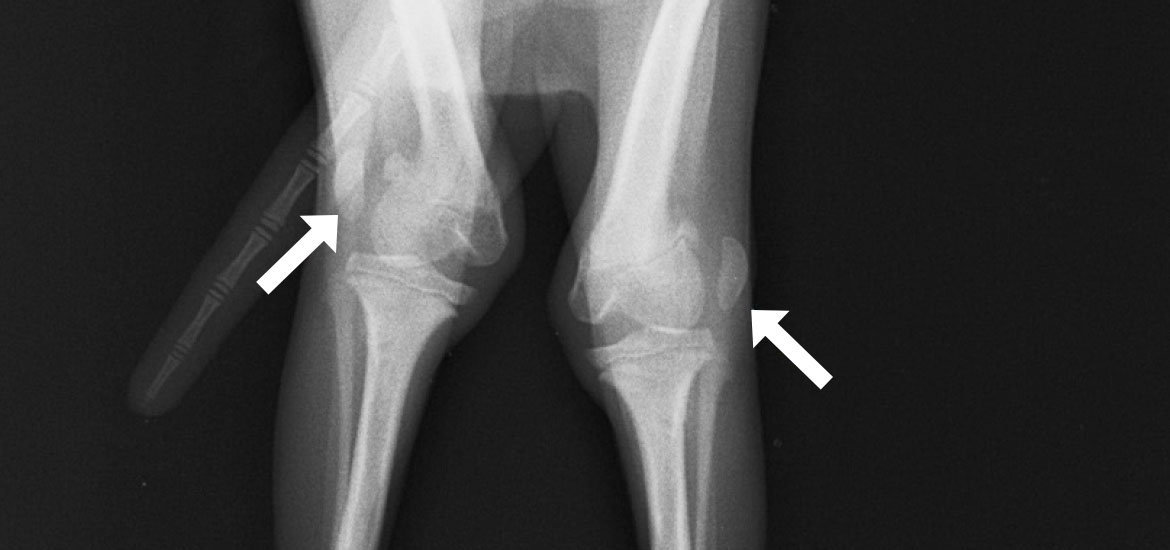

外方脱臼(両後肢)

-

Before

外方脱臼によりX脚に -

After

膝蓋骨が整復され、脚も真っ直ぐになりました